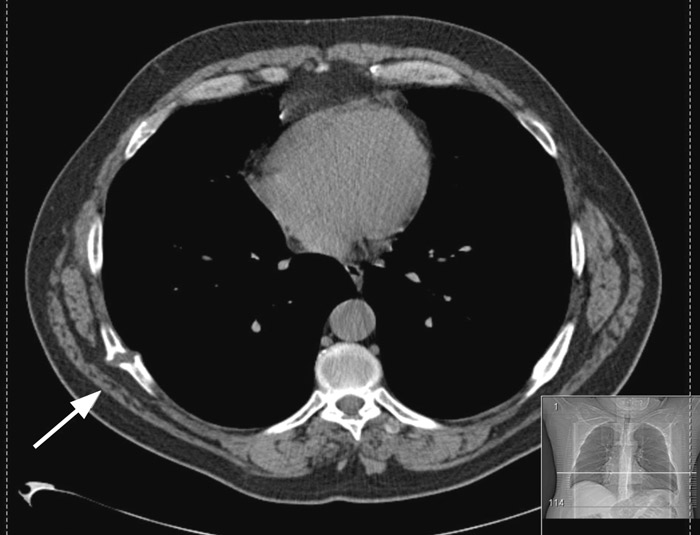

En 56 år gammel mann hadde i flere måneder vært plaget med smerter fra en lokal hevelse i ryggen. Han ble henvist til kirurgisk poliklinikk med spørsmål om tumor. Ved klinisk undersøkelse fant man en 10 × 10 cm stor tumor lokalisert på høyre side paravertebralt i torakalnivå. CT viste psedartrose dorsolateralt i 7. costa (bildet til venstre). Man valgte å avvente utviklingen. Han var til flere kontroller uten subjektiv eller røntgenologisk (CT) bedring.

Gjennom et lite snitt ble pseudartrosen og tilgrensende friskt bein resecert. Resektatet målte 4 cm (bildet til høyre). Histologisk undersøkelse viste pseudartrose. Det postoperative forløpet var ukomplisert. Halvannen måned etter operasjon hadde pasienten seponert samtlige analgetika og var smertefri.